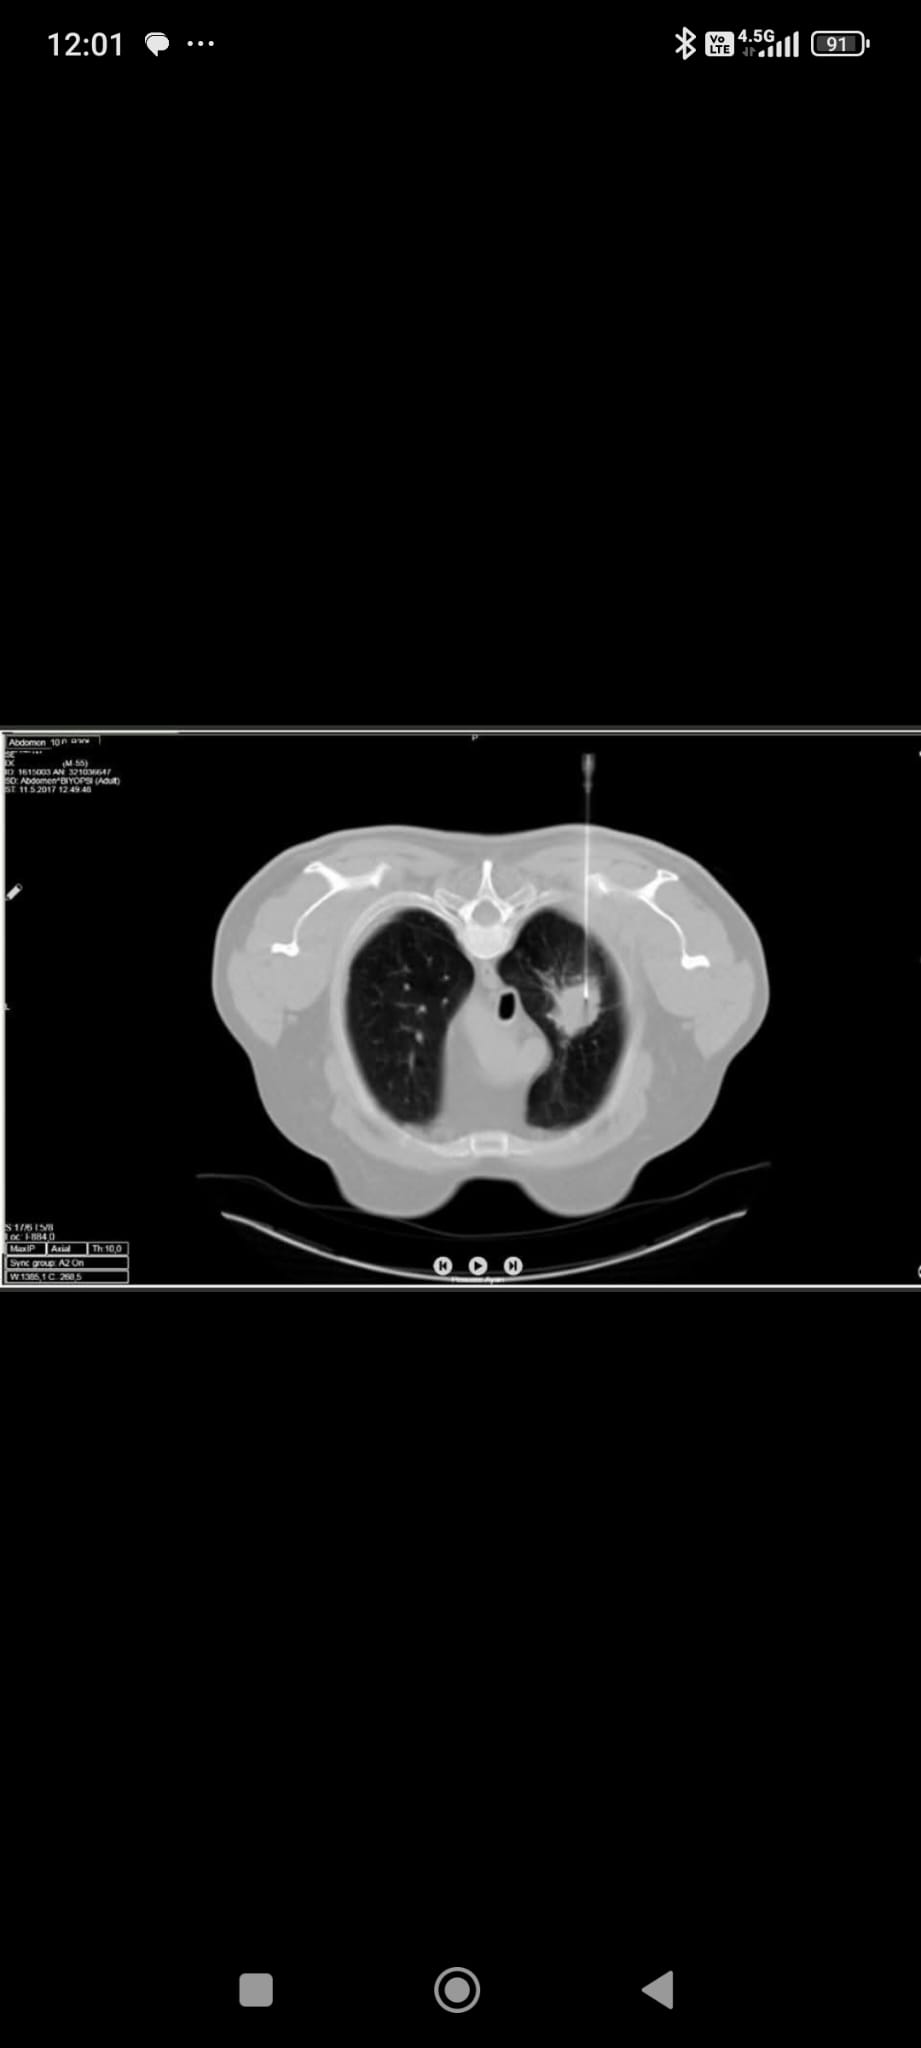

TİGRİS HABER - Dr. Ayhan Şenol, girişimsel radyolojinin; anjiyografi, ultrason, bilgisayarlı tomografi ve MR gibi ileri görüntüleme yöntemlerini rehber olarak kullandığını belirterek, “Bu branş, klasik cerrahi yöntemlerin aksine, tedavileri ameliyatsız olarak yapar. İşlemler çoğunlukla küçük bir iğne deliğiyle gerçekleştirilir ve vücutta yara izi kalmaz. Bu nedenle ‘mini cerrahi’ olarak da adlandırılır” dedi.

Dr. Ayhan Şenol, özellikle kanser tanısında kullanılan iğne biyopsilerinin, geçmişe göre çok daha sık ve güvenli şekilde uygulandığını ifade etti. “Biyopsi işlemi lokal anestezi ile hastanın rahat bir pozisyonda olduğu ortamda yapılır. İşaretlenen bölgeye özel bir biyopsi iğnesi ile ulaşılır, işlem sırasında hafif bir basınç hissi olabilir ancak bu normaldir. Sonrasında bölgeye basınç uygulanarak kanama riski önlenir ve pansumanla işlem tamamlanır” dedi. Biyopsi işlemlerinin toplumda yeterince bilinmediğine dikkat çeken Dr. Şenol, bu işlemlerin kanserin tanısı kadar genetik analizlerle tedavi planlamasına da büyük katkı sunduğunu dile getirdi.